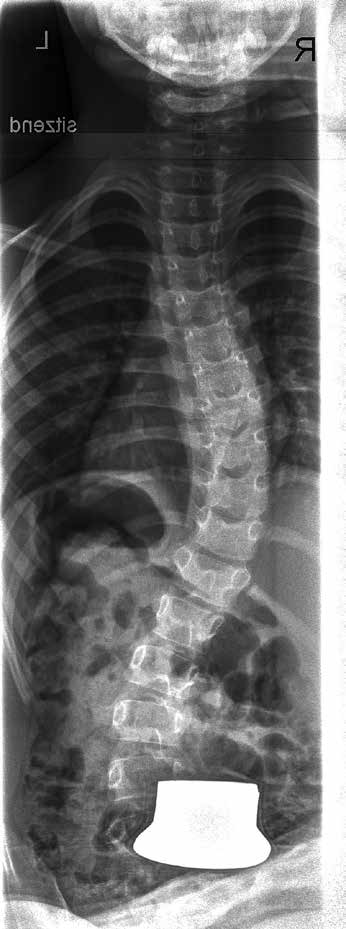

Einige Beispiele sollen die Möglichkeiten und Grenzen der Korsettversorgung bei neuromuskulären Fehlstellungen der Wirbelsäule verdeutlichen. Die Abbildungen 9 u. 10 zeigen einen Patienten mit ICP und einer schweren dekompensierten Skoliose. Er ist ohne Korsett nicht mehr sitzfähig. Mit Korsett konnte eine Sitzfähigkeit in der Sitzschale über den ganzen Tag, mit zwei Pausen von jeweils 45 Minuten, erreicht werden.

Bei der 7‑jährigen Patientin mit einer Skoliose bei ICP, die auf den Abbildungen 16 u. 17 zu sehen ist, konnte eine Verbesserung der Krümmung von 34° auf 18° erreicht werden.